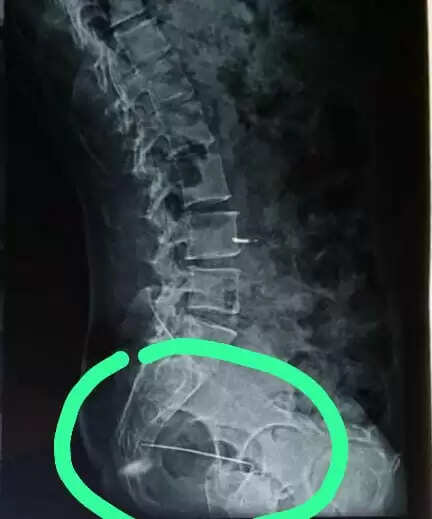

जटिल सर्जरी: रीढ़ व कूल्हे के बीच धंसी 6 सेंटीमीटर की सुई सफलतापूर्वक निकाली

अजमेर, 31 जुलाई(हि.स.)। अजमेर के चिकित्सकों ने एक अत्यंत जटिल और जोखिमपूर्ण सर्जरी को सफलतापूर्वक अंजाम देकर 43 वर्षीय महिला को राहत दी है। महिला की रीढ़ की हड्डी और कूल्हे के बीच गहराई में धंसी हुई 6 सेंटीमीटर लंबी सुई को मित्तल हॉस्पिटल एंड रिसर्च सेंटर के ब्रेन व स्पाइन सर्जन डॉ ए. आर गौरी एवं आर्थोपेडिक सर्जन डॉ दीपक जैन की अगुवाई में चिकित्सकों की टीम ने जटिल सर्जरी के बाद सुरक्षित रूप से बाहर निकाला।

पीड़ित महिला रामगंज क्षेत्र की निवासी हैं, जो पहले भी हार्ट सर्जरी से गुजर चुकी हैं और कमर के नीचे के हिस्से में शिथिलता की समस्या से जूझ रही थीं। कुछ समय से उन्हें नींद में भी असहनीय पीड़ा हो रही थी, जिससे चिंतित परिजनों ने प्रारंभिक तौर पर इसे बिस्तर पर लेटे रहने के कारण उत्पन्न बेडसोर समझा। बाद में बैठने की अवस्था में अत्यधिक पीड़ा होने पर पीड़ित को रेलवे हॉस्पिटल के ऑर्थोपेडिक विभाग में दिखाया गया। रेलवे हॉस्पिटल में हुई जांच में यह चौंकाने वाला तथ्य सामने आया कि रीढ़ और कूल्हे के बीच सुई धंसी हुई है।

डॉ. गौरी ने बताया कि पीड़िता बचपन से हार्ट पेशेंट होने के साथ.साथ निचले शरीर की कमजोरी से पीड़ित हैं, जिससे यह ऑपरेशन और भी जोखिमपूर्ण हो गया था। ऑपरेशन से पूर्व महिला की सभी आवश्यक जांचें करवाई गईं और फिर पूरी सावधानी व सटीकता के साथ सुई को निकाला गया।

सर्जरी के सफलतापूर्वक संपन्न होने के बाद महिला अब पूरी तरह स्वस्थ हैं और उन्हें अस्पताल से छुट्टी दे दी गई है। जांच में सामने आया कि महिला घर पर सिलाई.कढ़ाई का कार्य करती थीं और संभवतः बिस्तर पर पड़ी सूई करवट लेते समय शरीर में धंस गई, जिसका उन्हें पता तक नहीं चला।